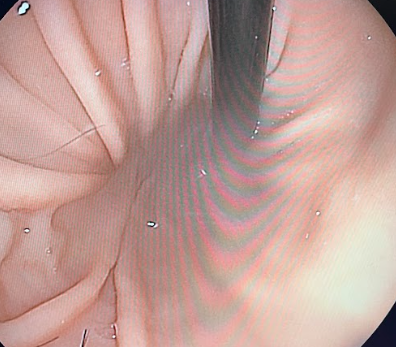

しかし数日後、再び貧血の進行が認められ原因究明と治療を急ぐ必要があったため、麻酔下にて出血点の精査のためのCT検査と内視鏡検査、歯肉炎に対して歯科処置(抜歯)を行いました。

内視鏡検査にて消化管内の出血は認められませんでした(写真は胃内)。